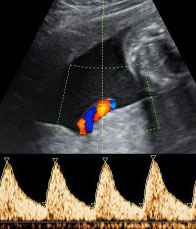

| Dopplersonographie |

(ab 26+0 SSW) |

€ 180,- |

| Dopplersonographie bei Zwillingen |

(ab 26+0 SSW) |

€ 350,- |